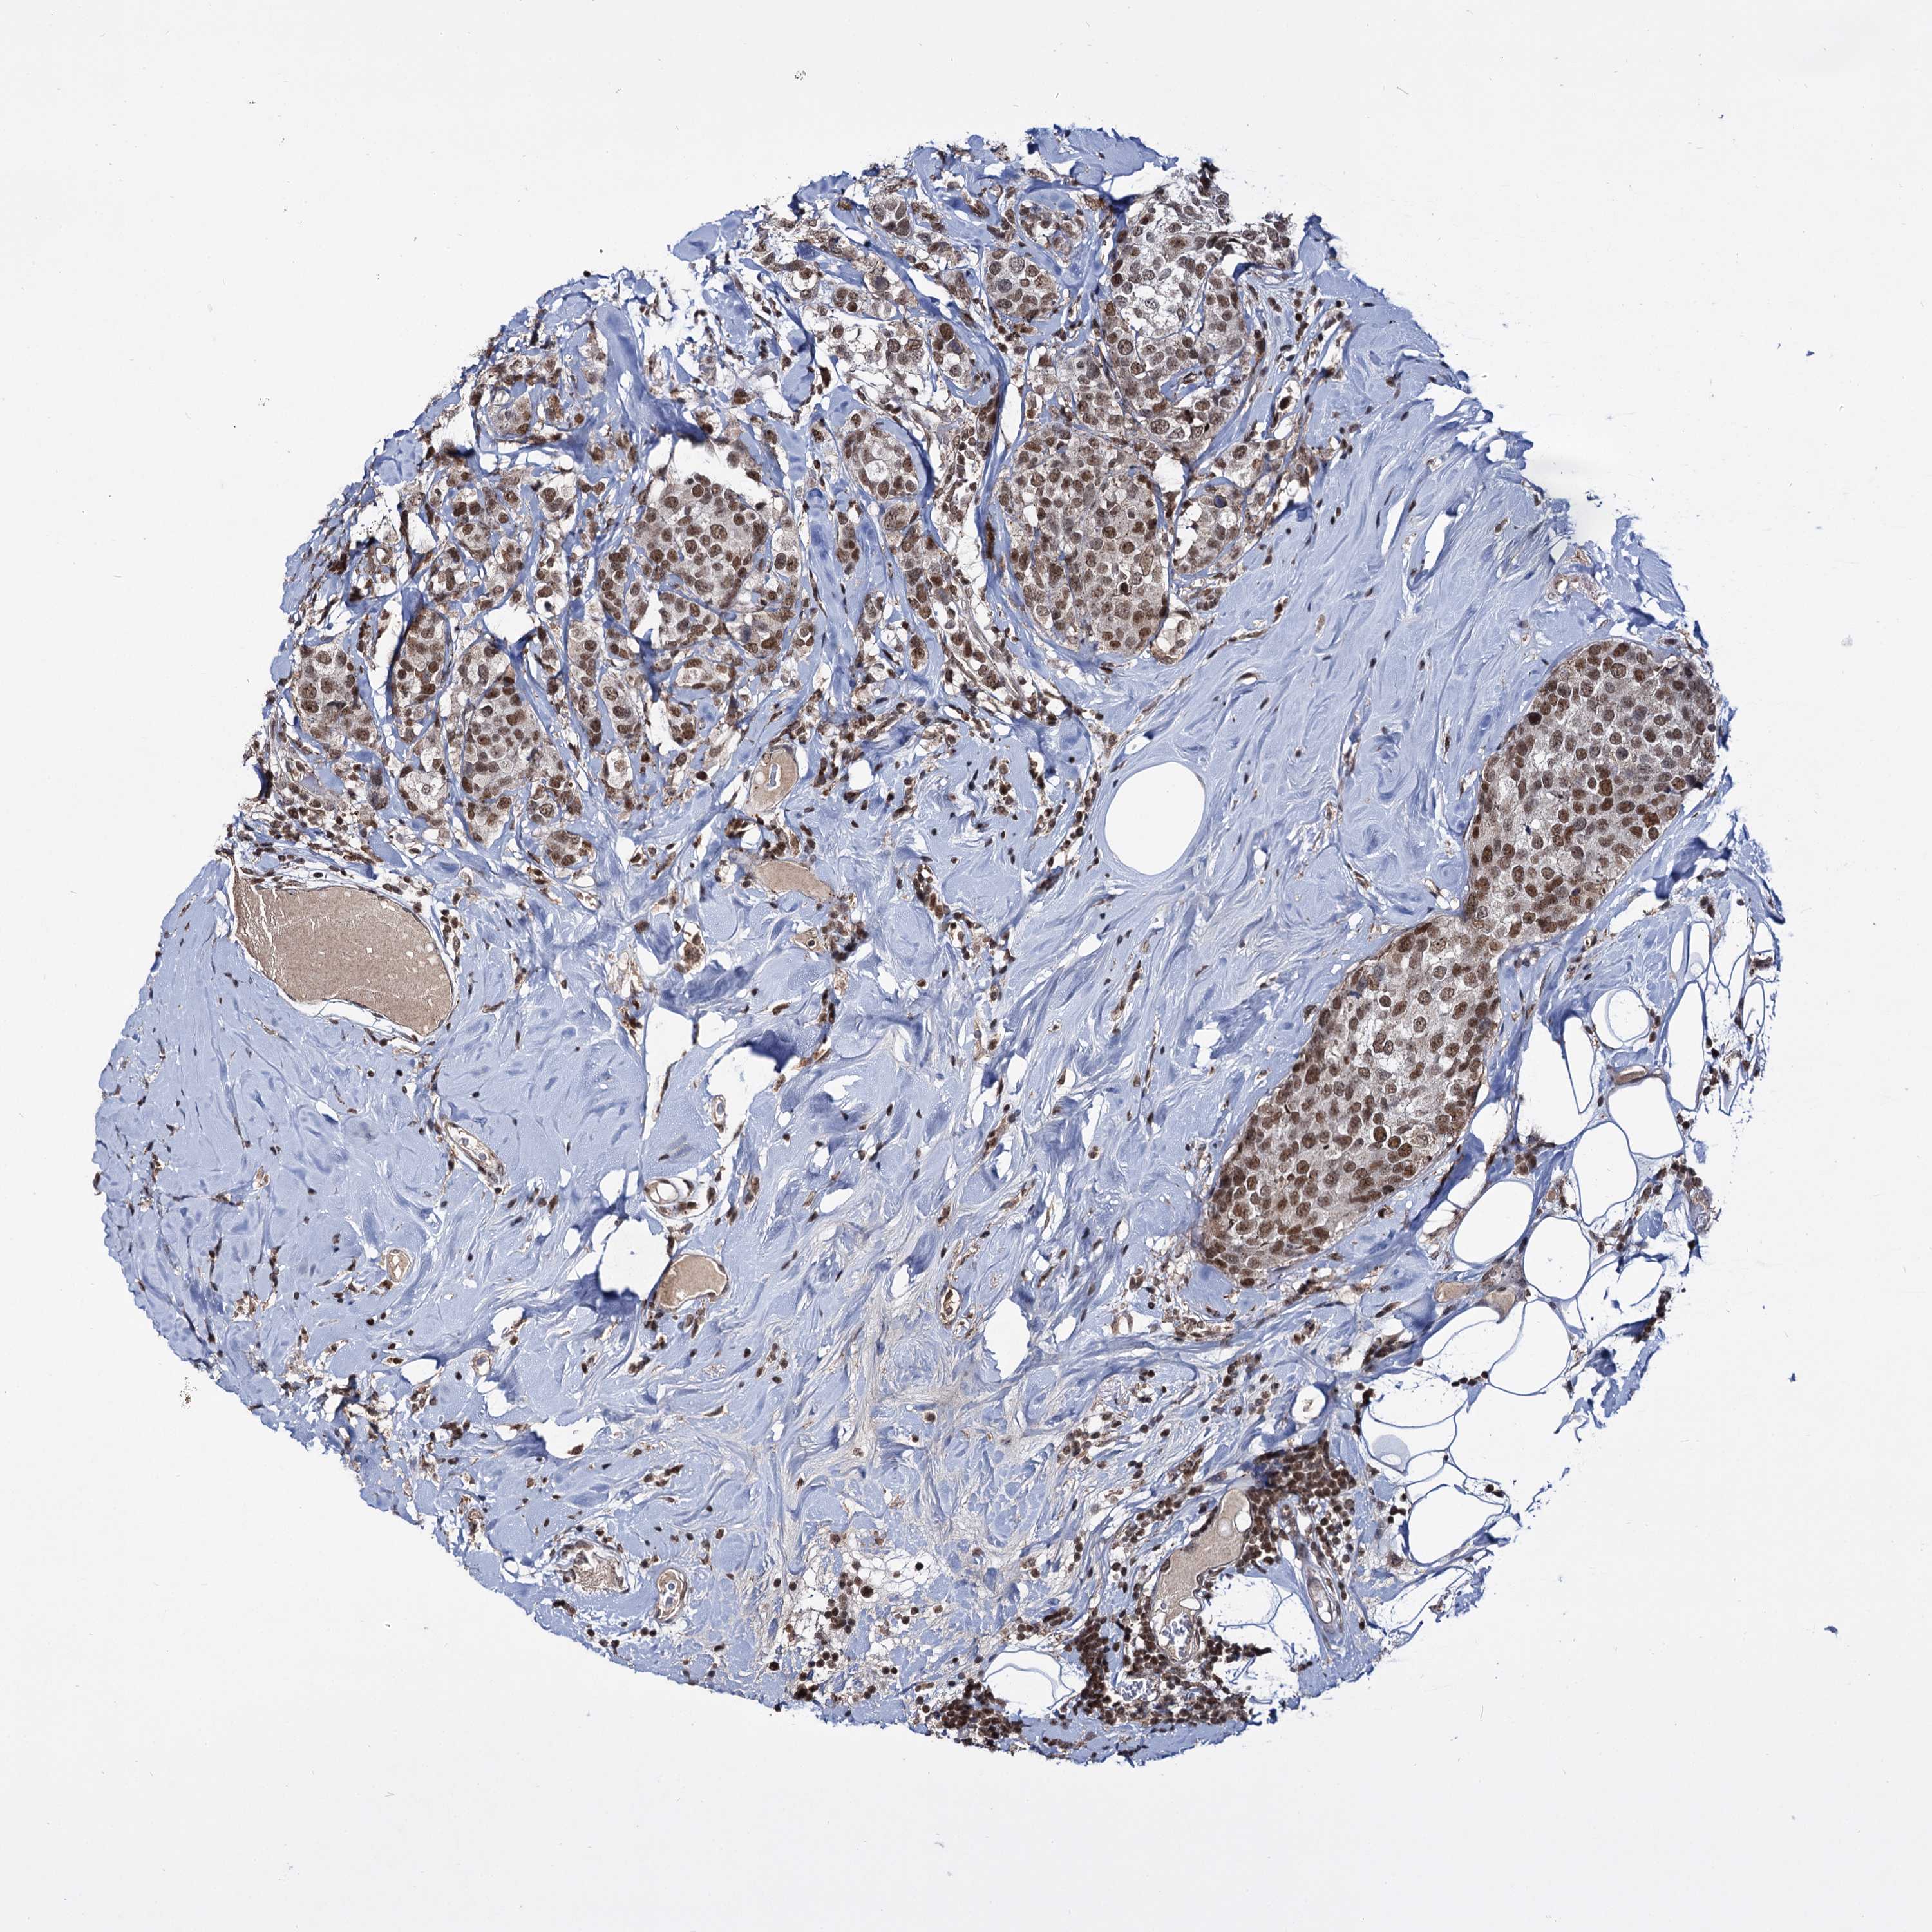

BRCA TCGA BRCA VALIDATION PROTEIN EXPRESSION

ANTIBODIES

AND

VALIDATION